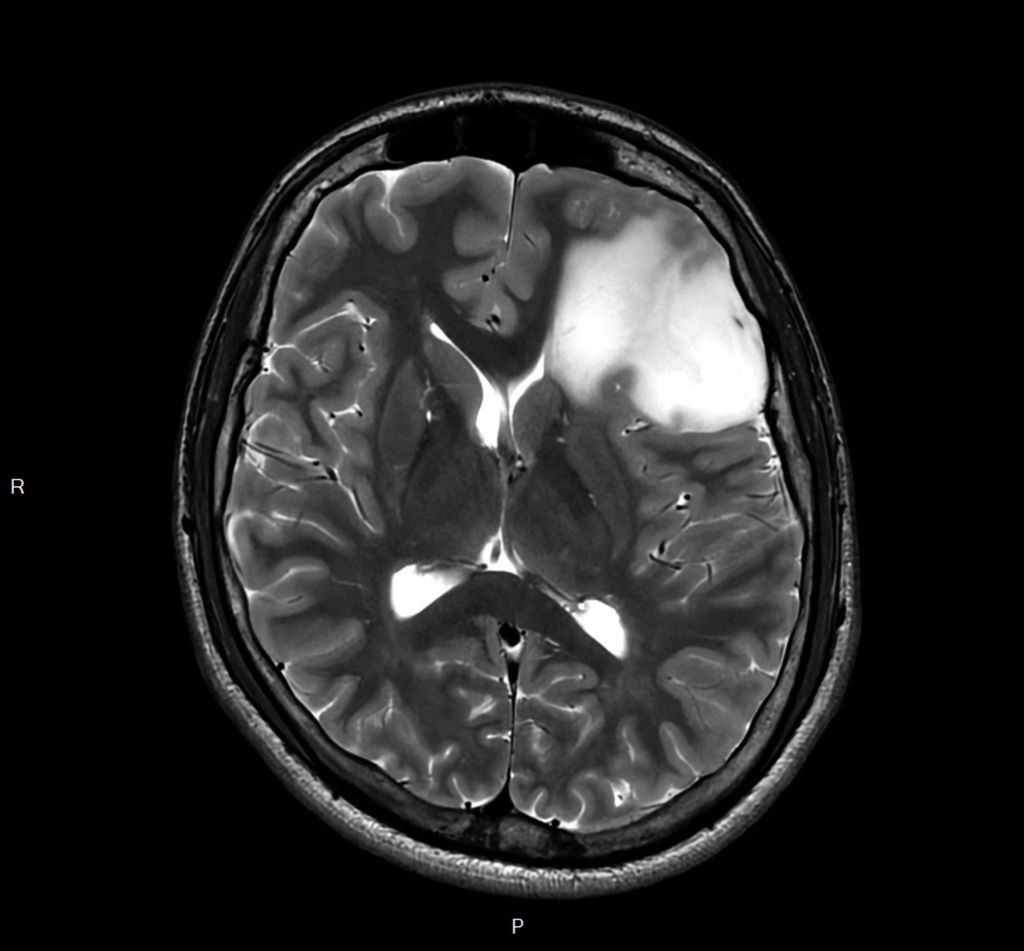

Fig.1: Image IRM d’un astrocytome de grade2 de l’OMS dans le lobe frontal gauche. Séquence T2